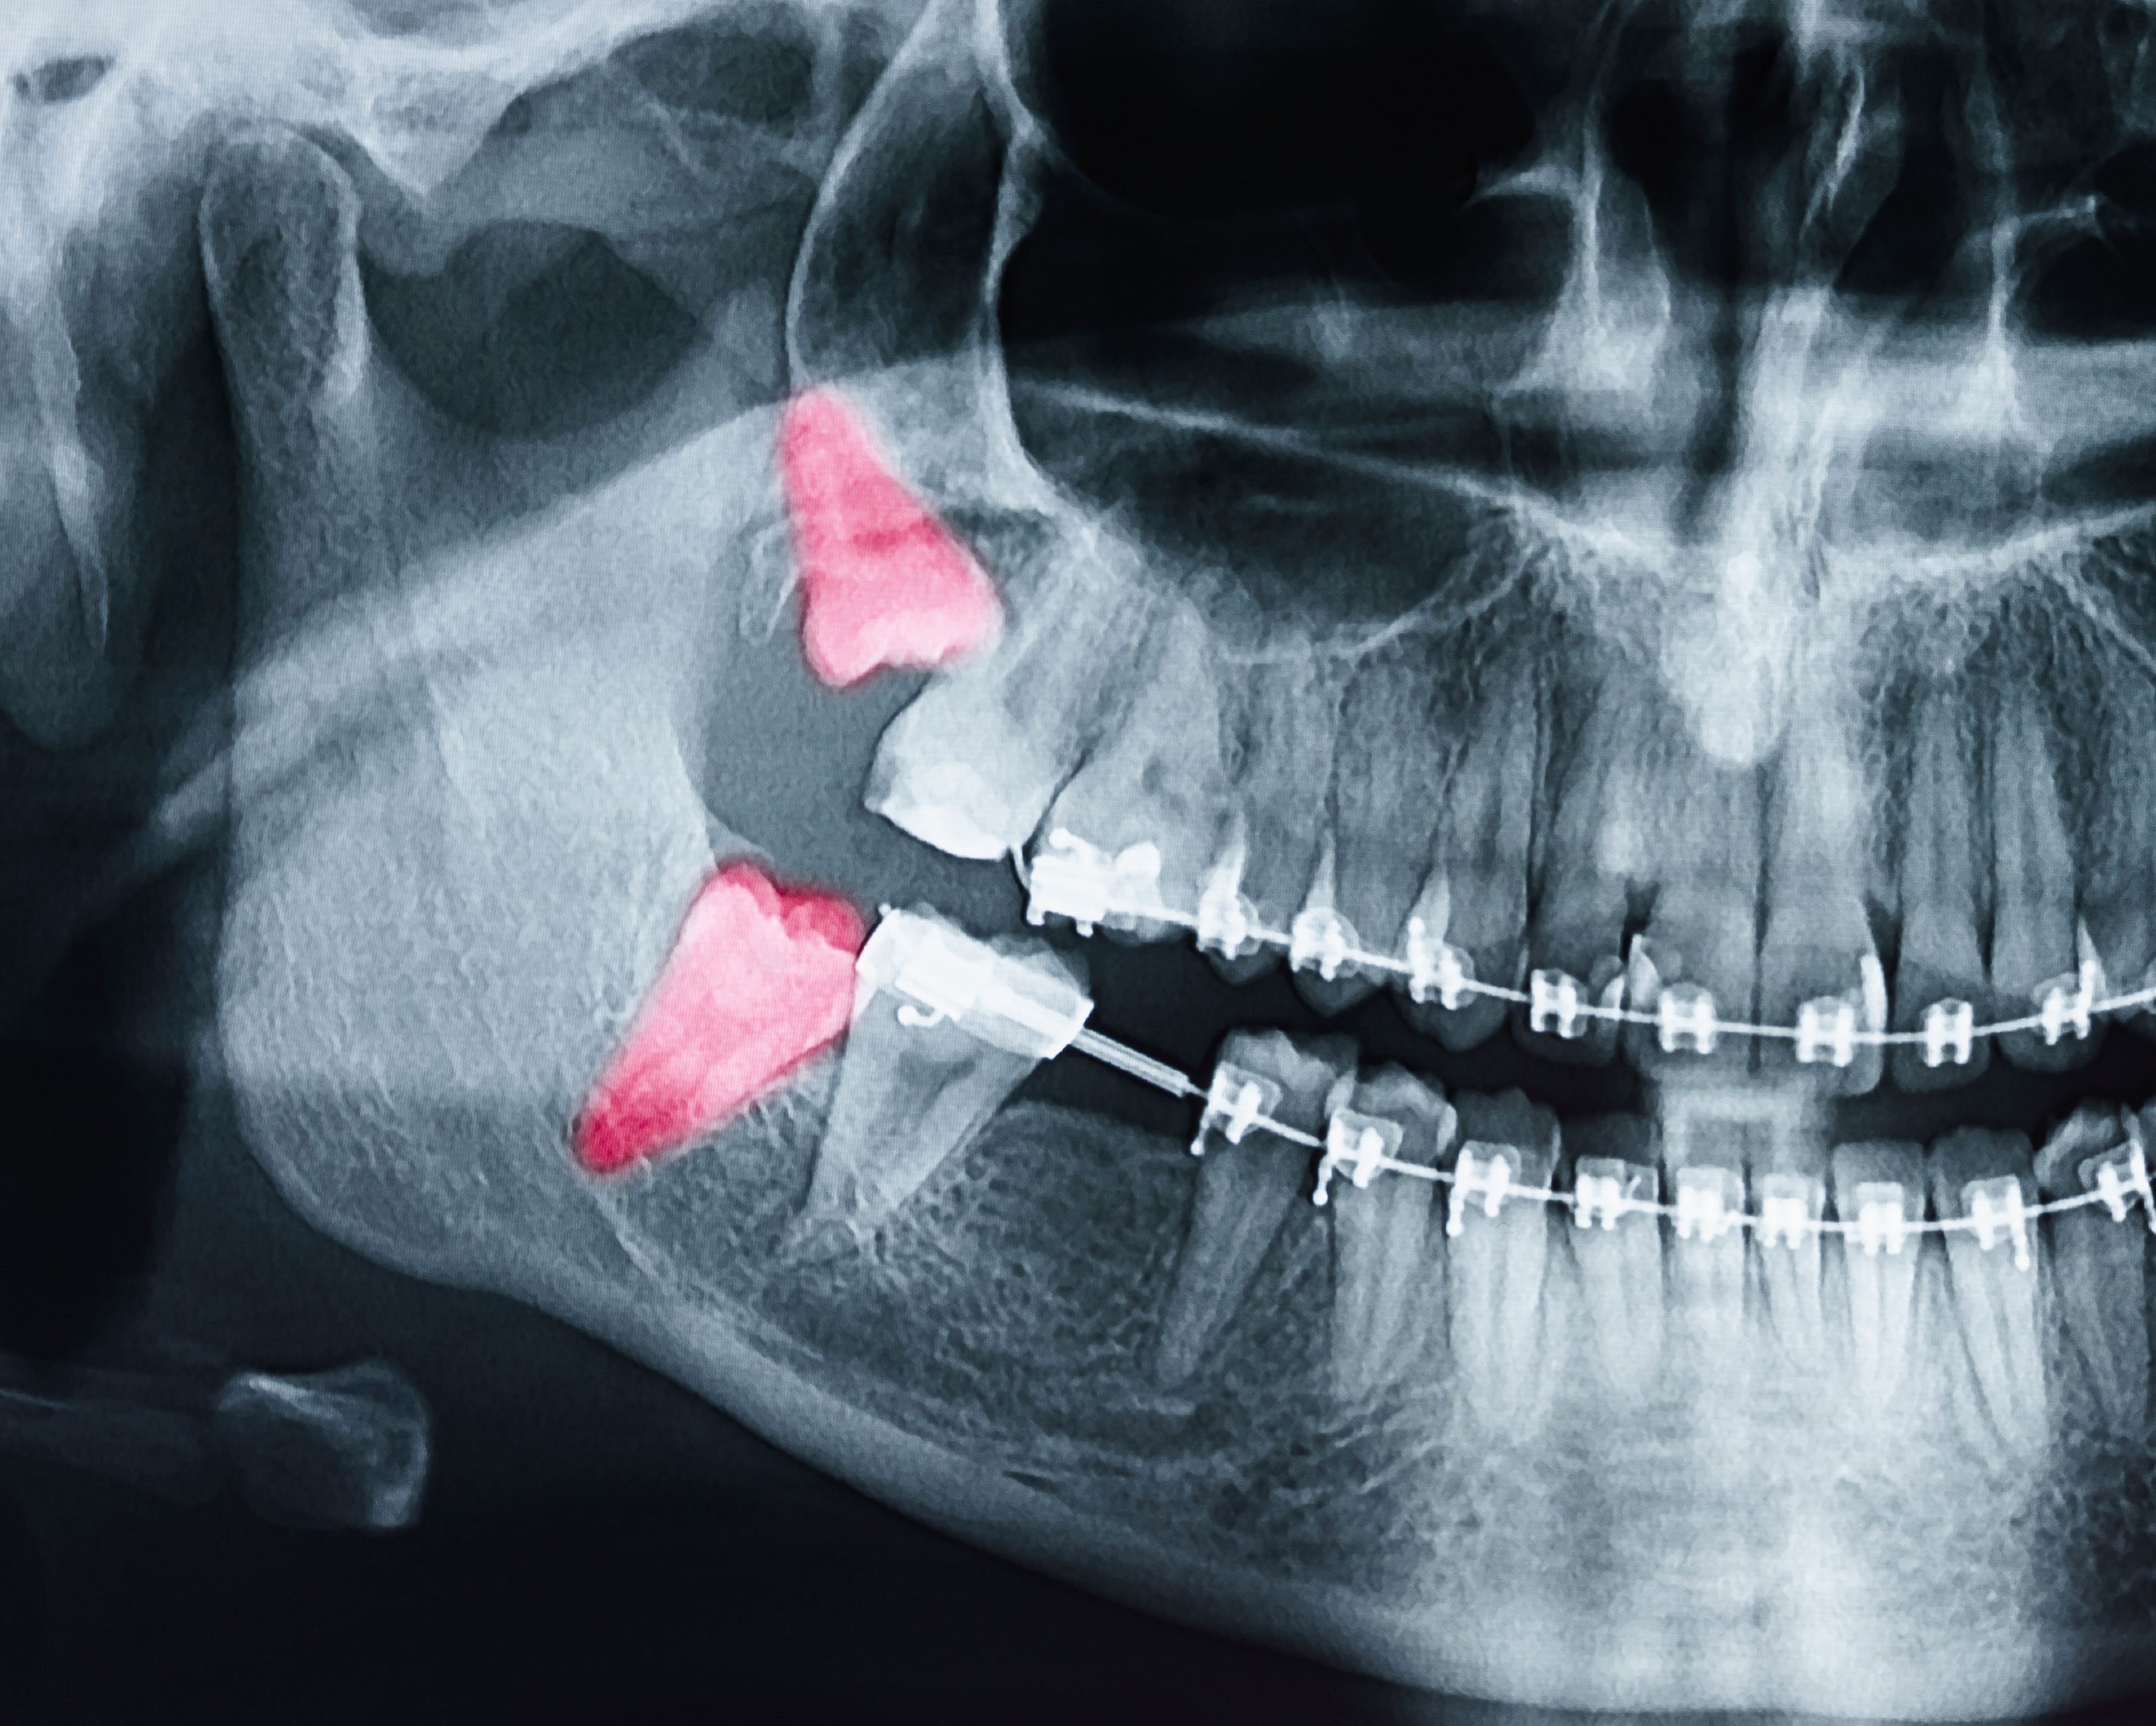

A wisdom tooth is considered impacted when it is submerged under gum tissue or bone and unable to erupt into position. Based on the type and amount of overlying tissue, impactions are classified in a few different ways. Soft tissue impactions occur when a wisdom tooth remains covered by gum tissue. If a wisdom tooth remains completely, or partially obstructed by bone, it's known as a bony impaction.